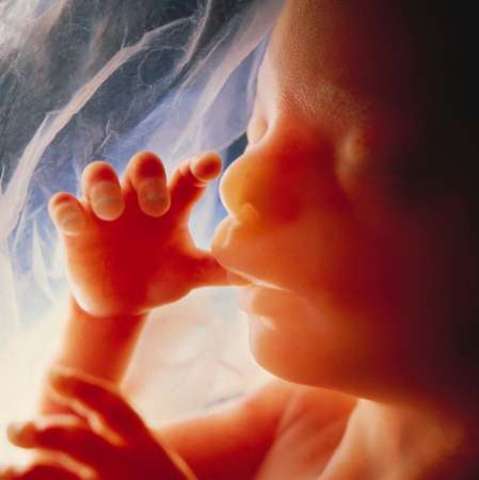

Once the major organs have been developed the developing child will become a fetus. Fetus organs will start to work and will start to interact with other body parts. Fetus size and weight will increase rapidly. A lot of complex process and signaling will happened during this stage includes gender specification which happened in the period between weeks 8 to 24. During this stage most of the fetus organs will be working. The fetus will start to interact with the outer world. The fetus will be

8 weeks to brith